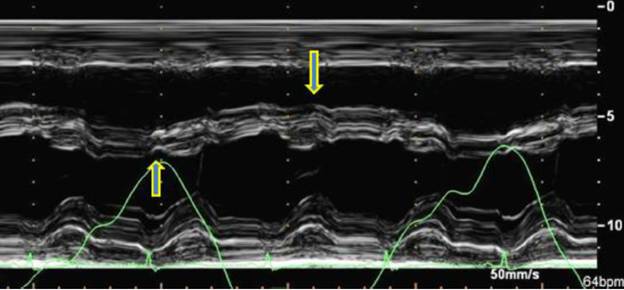

M型:室间隔运动随呼吸变化 typical CP